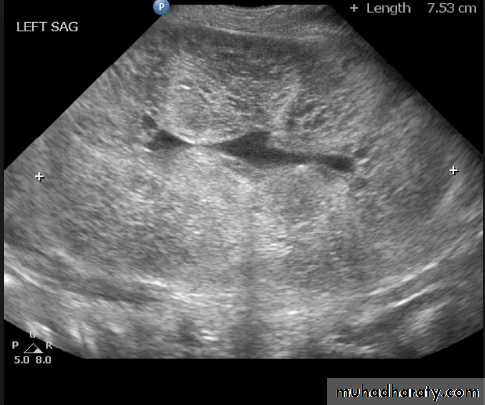

The opposite kidney shows compensatory

hypertrophy .

- Can be diagnosed as absent kidney on ultrasound or CT.